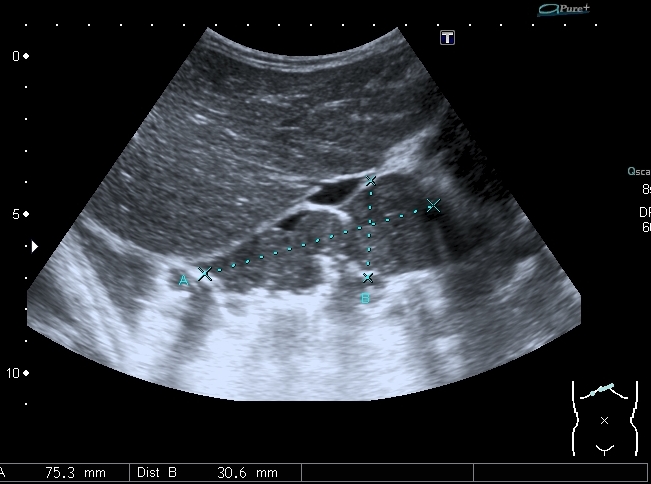

Предлагаю интересные изображения, полученные при сканировании лёгких через межрёберные промежутки и печень у ребёнка 4-х лет с подозрением на пневмонию

участок безвоздушной легочной ткани....похож на печень...пневмония в стадии опеченения... ;)

Согласен в отношении нижней доли правого лёгкого, изменения в ней похожи на сливную инфильтрацию при пневмонии, хотя носят несколько многоузловой характер. Но то что мы видим со спины в левом лёгком на пневмоническую инфильтрацию не похоже.

Добавляю сканы печени, я думаю они являются хорошей подсказкой о природе изменений в лёгких

Всё левое подреберье было выполнено опухолевым конгломератом, источником его я предположил левую почку, хотя разобраться , где почка, селезёнка, а тем более надпочечник я не смог.

По сложившейся тактике при обнаружении опухолевых образований мы не занимаемся морфологической верификацией, а отправляем ребёнка в головное учреждение, наверное это правильно - в лечении детских опухолей иногда бывают важны даже часы. Тем не менее , по УЗИ картине больше данных за нефробластому - есть остатки деформированной собирательной системы в области нижнего полюся образования, там же - немного ткани, похожей на нормальную почечную.